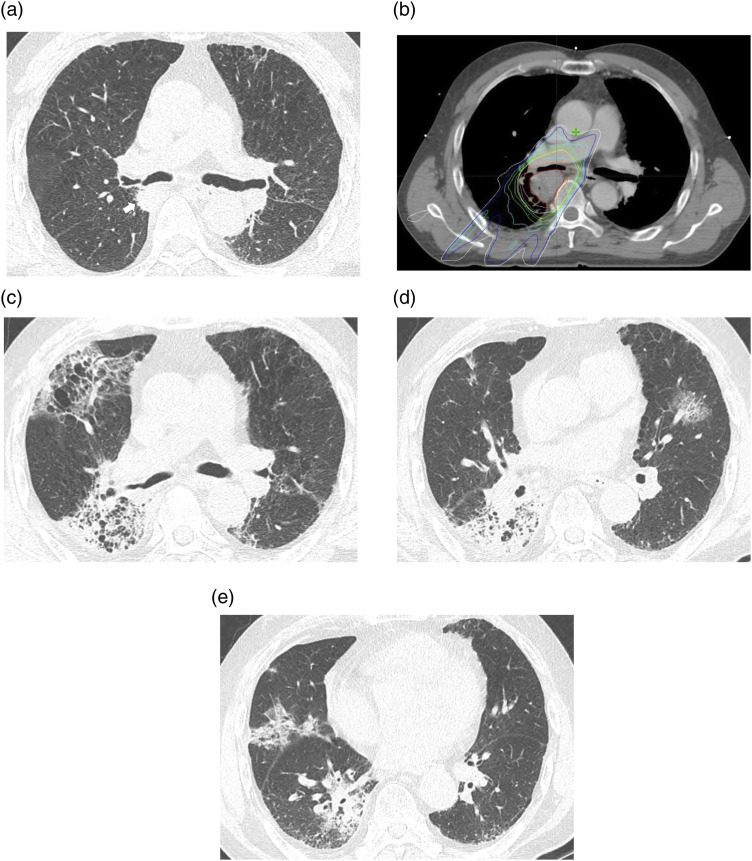

Materials and methods: We reviewed data from 240 NSCLC patients who underwent RT between 2014 and 2022. CT findings of RP were evaluated for parenchymal abnormalities and distribution, which were then classified into three patterns: localized pneumonia (LP), cryptogenic organizing pneumonia (COP), and acute interstitial pneumonia (AIP). Clinical outcomes of RP were evaluated based on Common Terminology Criteria for Adverse Events (CTCAE) grade.

Results: Of the 153 patients, 135 developed RP. The most common pattern was LP (n = 78), followed by COP (n = 30) and AIP (n = 25). Among the three CT patterns, CTCAE grade and days between the start of RT and the onset of RP (RT-RP days) were statistically significantly different (p < 0.05). The patients with AIP patterns exhibited higher CTCAE grade, and fewer RT-RP days compared to those with non-AIP patterns (p < 0.05). In these patients, lung-to-lung metastasis and underlying interstitial lung abnormality were observed more frequently (p < 0.05). Underlying pulmonary fibrosis, the AIP pattern, and higher CT extent scores were more frequently observed in higher CTCAE grade group (p < 0.001). In multiple regression analysis, age, bilateral distribution, RT-RP days, and CT extent score ≥3 were independent predicting factors for higher CTCAE grade.

Conclusions: RP in NSCLC patients can be classified into LP, COP, and AIP patterns and they exhibit different severities in clinical outcomes.